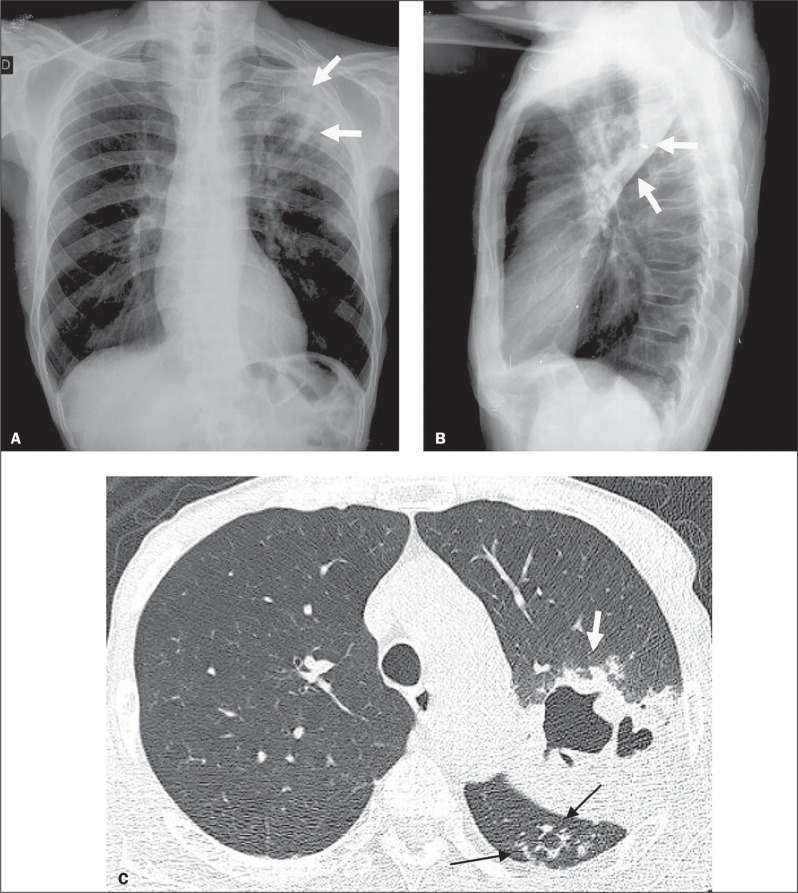

Although kidney transplantation is the best therapeutic option for patients with chronic kidney disease, the immunosuppression required greatly increases susceptibility to infections that are responsible for high post-transplant mortality. Pulmonary tuberculosis (TB) represents a major cause of such infections, and its early diagnosis is therefore quite important. In view of that, we researched the manifestations of active pulmonary TB in kidney transplant recipients, through chest X-ray and computed tomography (CT), as well as determining the number of cases of active pulmonary TB occurring over a 3.5-year period at our institution. We identified four cases of active pulmonary TB in kidney transplant recipients. The CT scans provided information complementary to the chest X-ray findings in all four of those cases. We compared our CT findings with those reported in the literature. We analyzed our experience in conjunction with an extensive review of the literature that was nevertheless limited because few studies have been carried out in lowand middle-income countries, where the incidence of TB is higher.